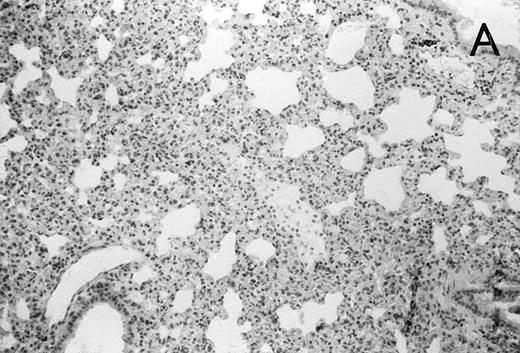

Histology further supported this observation. Control animals showed well-developed pneumonia with abscess formation (Fig3A) in their lungs, but in their livers, only small areas of inflammation with scattered microabscesses and foci of hepatic necrosis were observed (Fig 3B). In contrast, mice pretreated with G-CSF had only mild peribronchitic alterations in their lungs without signs of containment of inflammation such as abscess formation (Fig 4A). Livers and spleens of mice pretreated with G-CSF were severely altered, showing large abscesses which contained massive amounts of bacteria (Fig 4B). In addition, large necrotic areas surrounded by granulocytes were observed in the livers (Fig 4C). When MoAb III/5-1 was administered in addition to pretreatment with G-CSF, almost all changes observed in animals pretreated with G-CSF were reversed: there were only minor bronchial and peribronchial infiltrations by granulocytes (minimal change focal pneumonia), and the livers showed small microabscesses as observed in control mice. When treatment with G-CSF was started at 24 hours after bacterial challenge, a mixed pattern was observed. In the lungs, there was a beginning pneumonic reaction and a moderate perivascular and septal edema. However, in the liver there was almost no difference to the severe alterations observed in mice pretreated with G-CSF: huge abscesses loaded with bacteria joined extended necrotic areas.

(A) Micrograph of lung tissue 72 hours after intranasal infection with 1 × 103 CFU of K pneumoniae B5055. Lung abscess with severe tissue destruction in a PBS-treated control animal. Hematoxylin & Eosin (H&E); original magnification ×150. (B) Small foci of hepatic necrosis. H&E; original magnification ×600.